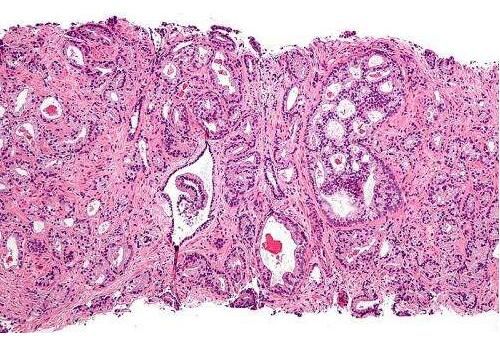

近日,一篇刊登在国际杂志International Journal of Cancer上题为"Mushroom consumption and incident risk of prostate cancer in Japan: A pooled analysis of the Miyagi Cohort Study and the Ohsaki Cohort Study"的研究报告中,来自日本东北大学公共卫生学院的研究人员通过研究发现,吃蘑菇或能帮助降低个体患前列腺癌的风险。

文章中,研究者对日本中老年男性进行研究后发现,吃蘑菇与个体患前列腺癌的风险之间存在一定的负相关关系,这就表明,经常吃蘑菇或有助于预防男性患前列腺癌。

研究人员共招募了36499名年龄在40-79岁之间的男性加入到了1990年的宫城县队列研究和1994年的大阪队列研究中,研究者对参与者的平均随访时间为13.2年,在研究过程中,3.3%的参与者患上了前列腺癌,相比每周摄入蘑菇不足一次的参与者而言,每周摄入蘑菇1-2次的参与者患前列腺癌的风险会降低8%,而每周摄入3次甚至更多蘑菇的参与者而言,其患前列腺癌的风险则会降低17%。

研究者Shu Zhang说道,这项研究中我们并未收集到关于参与者摄入蘑菇种类的信息,因此我们很难知道到底是哪一类蘑菇促成了我们的研究发现,此外目前研究人员也并未阐明蘑菇预防前列腺癌风险的分子机制,后期研究人员还将继续深入研究阐明其中的分子机制。(生物谷Bioon.com)